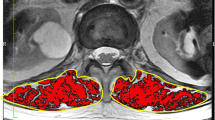

The L1 vertebra geometry was segmented and reconstructed from CT images (Fig. 1), obtained by means of Toshiba Aquilion Prime, of a non-osteoporotic 60-year-old female. The slice thickness of CT images was 1 mm. Image segmentation and three dimensional geometry reconstruction were performed using Mimics v20 (Materialise Inc., Leuven, Belgium). Upper and lower polymethylmethacrylate (PMMA) plates were designed and assembled with L1 vertebra in order to reflect intervertebral disc spaces using the Materialise 3-matic v12 module in the Mimics software. A volume mesh was also performed using the Materialise 3-matic v12 module. Then the model was exported to the commercial finite element software ABAQUS 2019 (Dassault Systemes, Vélizy-Villacoublay, France) to perform a finite element analysis. A mesh sensitivity study was employed to confirm the appropriateness of this finite element mesh. Specifically, a mesh refinement study was performed, evaluating meshes with 7,373 to 58,728 elements. The mesh convergence check was also performed with the difference in von Mises stress at center of mid-transverse section of L1 vertebra less than 1.5%. The L1 vertebra with PMMA plates was thus represented by a finite element model consisting of 29,364 tetrahedral elements. The geometry of the L1 vertebra model was validated with published human cadaveric studies using quantitative anatomy of lumbar [23, 24]. This project was approved by the ethical committee, faculty of medicine, Prince of Songkla University (REC.61–364-25–2).

The Young's modulus was assigned on element by element basis and it depended on the local bone density. For the healthy case, the Young’s modulus varied between 0.56 MPa and 10.71 GPa. The distribution of Young’s modulus in mid-transverse and mid-sagittal sections of L1 vertebra is shown in Fig. 2. We then mimicked the osteoporotic bone conditions by decreasing Young’s modulus in each region by 25% for an osteoporotic bone and 50% for a severe osteoporotic bone (as shown in Table 1).